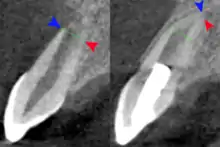

The secondary therapeutic goal of regenerative endodontic procedures is continued root development. A study has shown that teeth treated with revascularization showed a significantly greater percentage increase in root length compared with teeth treated by either MTA apexification or calcium hydroxide apexification MTA apexification procedures. Regenerative procedures promoted a decrease in apical diameter (apical closure). Root development allows the increase of the resistance to fracture and improve the tooth survival rate.[46]

Radiograph images, before and after the procedure are used to evaluate the outcome of the treatment. The patients are scheduled to follow up at 3, 6, 9, and 12 months after the completion of therapy. The tooth is accessed for different aspects such as pain, swelling, sinus tract, mobility, tooth discoloration, and the occlusion relationship. At the 12-month follow-up, CBCT images are taken to analyze the root development, in specific to access for the disappearance of apical radiolucency, increase of root length or a decrease of the apical foramen, or both.[50]